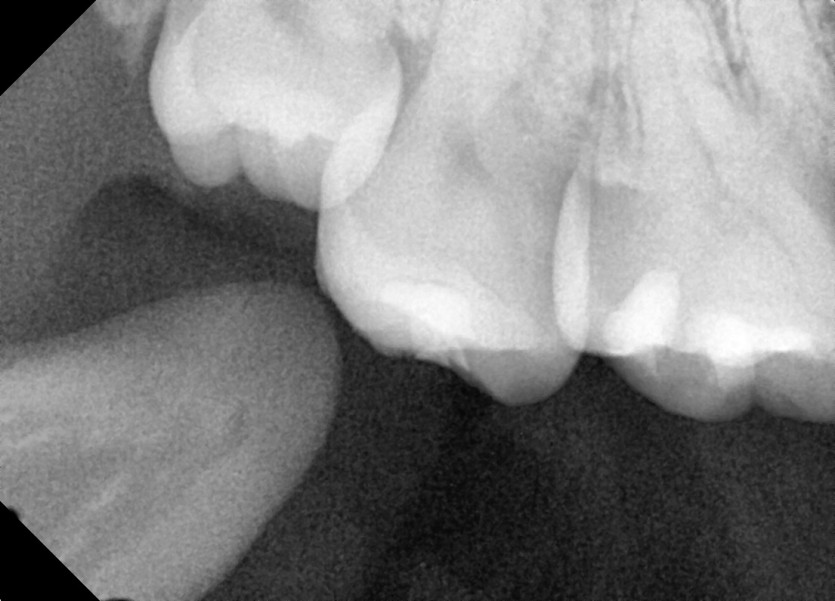

#18,48 사랑니 발치

구강 외과 전문의가 당일 발치했습니다.